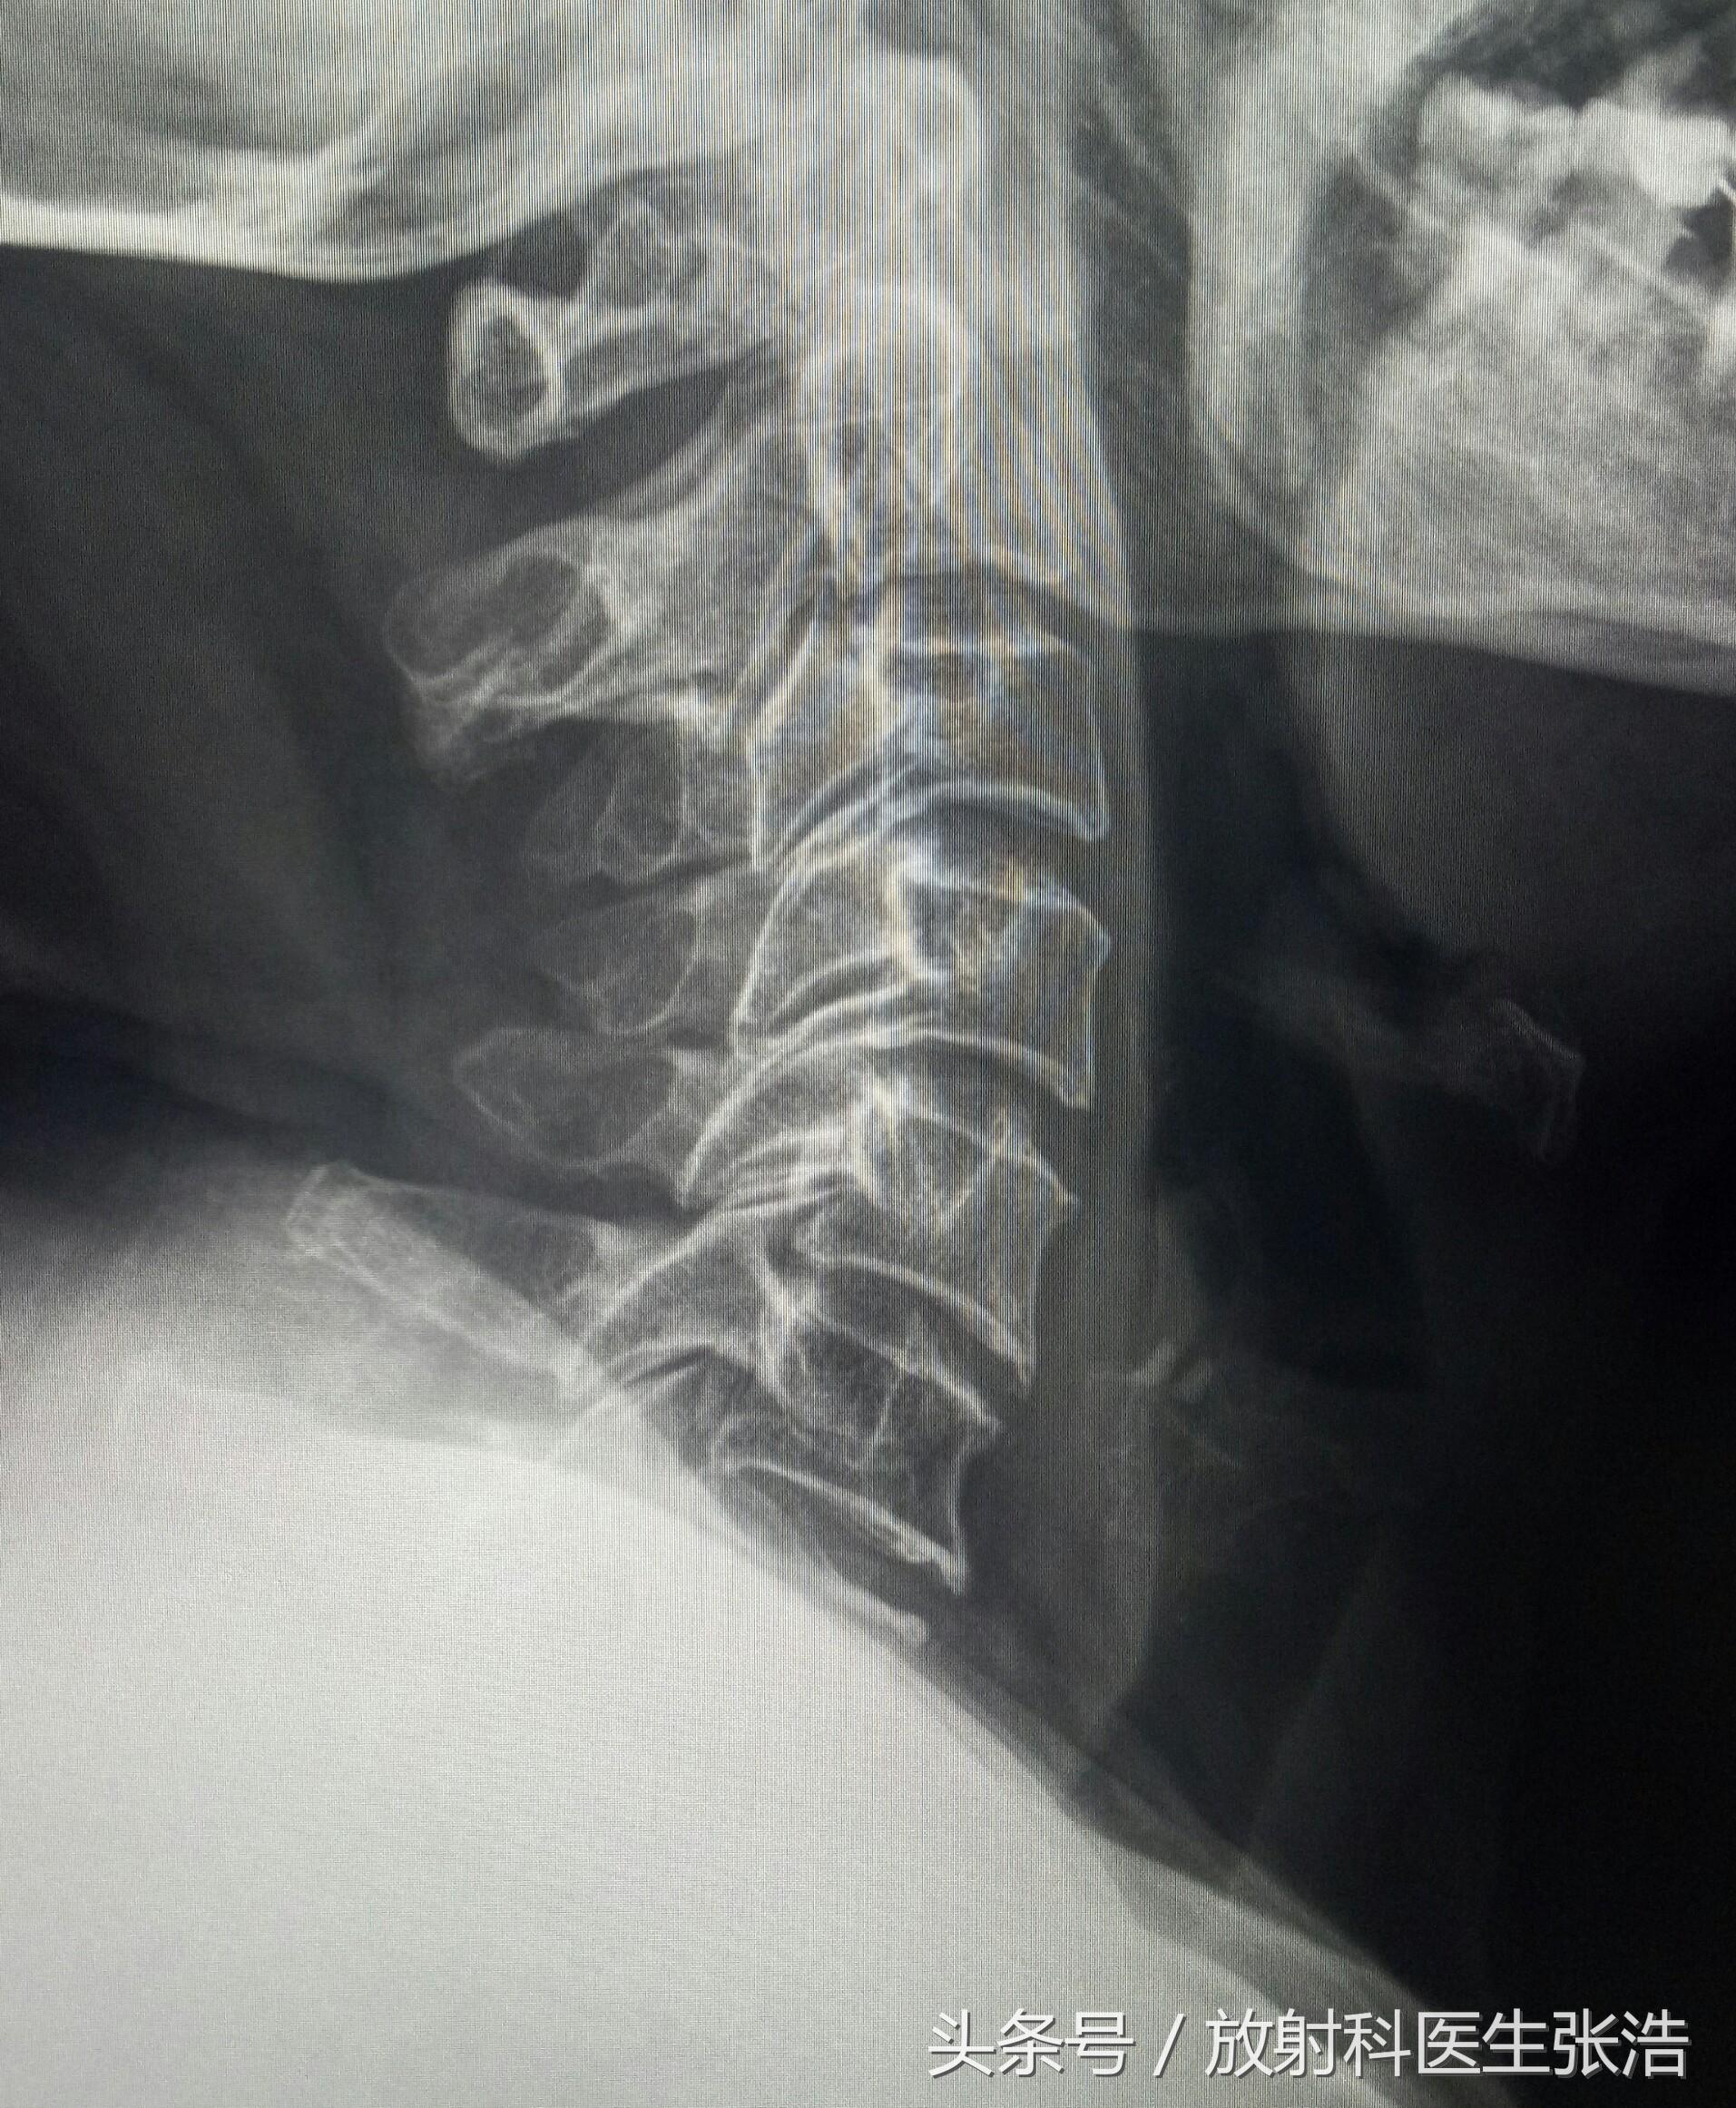

骨質(zhì)增生是一種常見的骨科疾病,嚴重影響著許多人的生活質(zhì)量,隨著醫(yī)學(xué)研究的深入,越來越多的藥物被用于治療和預(yù)防這種疾病,本文將為您介紹骨質(zhì)增生的十大特效藥,幫助您更好地了解并應(yīng)對這一健康問題。

在開始之前,讓我們先了解一下什么是骨質(zhì)增生,骨質(zhì)增生是一種骨科疾病,主要表現(xiàn)為關(guān)節(jié)軟骨的磨損和骨質(zhì)的增生,它可能導(dǎo)致疼痛、活動受限和其他不適,本文將介紹的十大特效藥,旨在幫助患者緩解病痛,改善生活質(zhì)量。